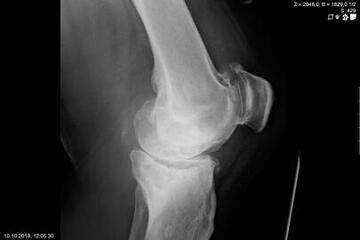

Endoprosthetics of the knee joint is an effective procedure for the treatment of symptomatic advanced wear and tear of the knee joint (gonarthrosis). If the X-ray shows a complete loss of joint space width under load, the complaints persist for more than 6 months, and the conservative therapy options have been exhausted, there is probably an indication for treatment with an artificial joint replacement (endoprosthesis). It must then be clarified which type of prosthesis is required, because today we have a large number of implants available. We distinguish between partial joints and full prostheses, and in the case of full prostheses we again distinguish between the degree of coupling of the prosthesis. If only parts of the joint are affected, only these have to be replaced and partial joints can be used. The so-called sled prostheses on the inner and outer side of the knee joint, as well as the sliding bearing replacement for problems on the kneecap, have both proven themselves effective. With full prostheses, we again differentiate between the degree of coupling of the prosthesis. Anterior and posterior cruciate ligament-supporting prostheses (surface replacement) partially coupled implants that support the inner and outer ligaments and coupled implants for complete loss of knee ligament and capsular function are used. Partially and fully coupled prostheses usually have to be inserted with stem components.